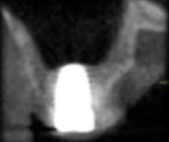

Técnica de ventana lateral en un tiempo: La literatura avala este procedimiento con tasas de sobrevida a largo plazo de los implantes similares a la técnica de ventana lateral en dos tiempos. No existe suficiente evidencia científica, para llegar a un consenso de altura ósea mínima. Se podría sugerir como medidas, 3 mm de altura y 5 mm de ancho, como mínimo de tejido óseo sub antral, a fin de lograr una buena estabilidad primaria9. Dicha estabilidad primaria depende no solo de cantidad sino también calidad, técnica y diseño del implante. Algunos trabajos muestran que las superficies rugosas tienen mejor tasa de sobrevida que los implantes maquinados10.